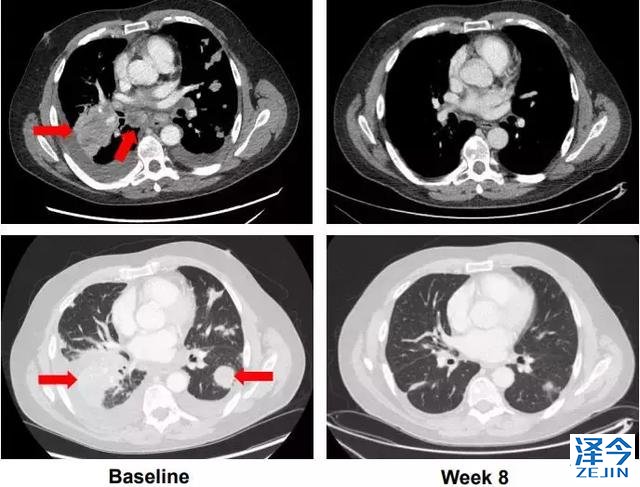

61岁男性转移性低分化甲状腺癌;NCOA4-RET融合阳性

在lenvatinib后出现进展,并有呼吸急促,胸痛的症状,LOXO-292治疗八周后评估,最大肿瘤减少-72%,并且患者的症状全部消失,已经重回工作岗位。